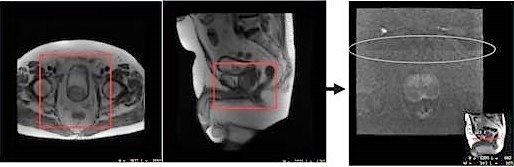

Figure 2. Scan acquired with no air around Phase FOV with end result of artifact

Scan acquired with air-to-air in the phase FOV with MUSE Diffusion. The addition of anterior and posterior saturation bands help to reduce motion and artifacts from fat.

Figure 3. Scan with air-to-air space around FOV